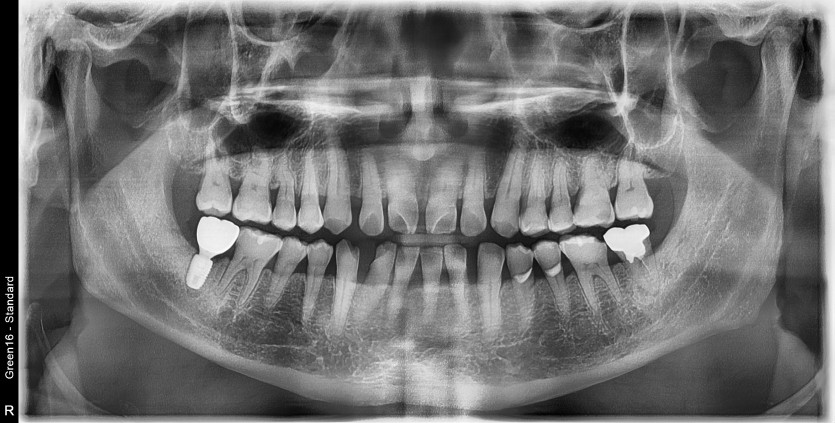

#48 사랑니 발치

구강 외과 전문의가 당일 발치했습니다.